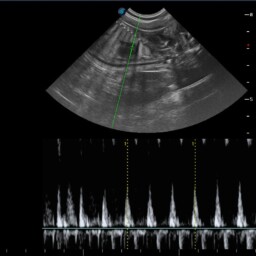

• Kontrola okresu okołoporodowego przy użyciu przenośnego urządzenia do pomiaru tętna płodów